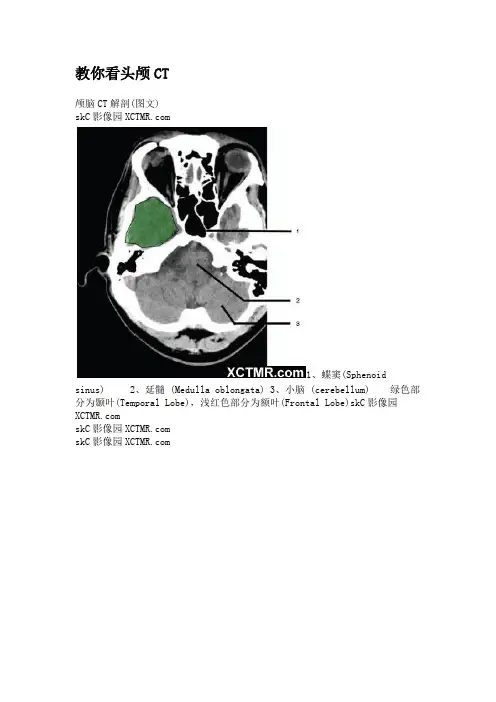

教你看头颅CT颅脑CT解剖(图文)skC影像园1、蝶窦(Sphenoid sinus)2、延髓 (Medulla oblongata)3、小脑 (cerebellum) 绿色部分为颞叶(Temporal Lobe),浅红色部分为额叶(Frontal Lobe)skC影像园 skC影像园skC影像园4、第四脑室(Fourth ventricle)5、小脑中角(Middle cerebellar peduncle)6、乙状窦(Sigmoid sinus)7、颞骨及乳突气房 (Petrous temporal bone and mastoid air cells)8、桥小脑角(Cerebellopontine angle)9、脑桥 (Pons) 10、垂体窝(Pituitary fossa) 绿色部分为颞叶(Temporal Lobe),浅红色部分为额叶(Frontal Lobe)skC影像园skC影像园 11、小脑蚓部(Cerebellar vermis) 12、基底动脉(Basilar artery) 13、桥前池 (Prepontine cistern) 14、鞍背 (Dorsum sellae) 15、侧脑室颞角(Temporal horn of lateral ventricle) 绿色部分为颞叶(Temporal Lobe),浅红色部分为额叶(Frontal Lobe)skC影像园skC影像园 16、环池 (Ambient cistern) 17、角间池 (Interpeduncular cistern) 18、大脑角 (Cerebral peduncle) 19、侧裂池 (Sylvian fissure) 绿色部分为颞叶(Temporal Lobe),浅红色部分为额叶(Frontal Lobe) skC影像园skC影像园 20、小脑上池 (Third ventricle) 21、侧脑室前角 (Frontal horn of lateral ventricle) 21a、第三脑室 (Third ventricle) 绿色部分为颞叶(Temporal Lobe),浅红色部分为额叶(Frontal Lobe),黄色部分为枕叶(Occipital Lobe)skC影像园skC影像园 22、尾状核头部 (Head of caudate nucleus) 23、岛叶 (Insular cortex) 24、外囊 (External capsule) 25、豆状核(Lentiform nucleus) 26、丘脑(Thalamus) 绿色部分为颞叶(Temporal Lobe),浅红色部分为额叶(Frontal Lobe),黄色部分为枕叶(Occipital Lobe)skC影像园skC影像园27、纵裂 (Interhemispheric fissure) 28、内囊前肢 (Anterior limb of internal capsule) 29、内囊膝部 (Genu of internal capsule) 30、内囊后肢(Posterior limb of internal capsule) 31、侧脑室三角区及脉络丛钙化(Trigone of lateral ventricle and calcified choroid plexus) 32、侧脑室枕角(Occipital horn of lateral ventricle) 绿色部分为颞叶(Temporal Lobe),浅红色部分为额叶(Frontal Lobe),黄色部分为枕叶(Occipital Lobe),褐色部分为顶叶(Parietal Lobe)skC影像园skC影像园33、侧脑室体部 (Body of lateral ventricle) 34、放射冠 (Corona radiata) 浅红色部分为额叶(Frontal Lobe),黄色部分为枕叶(Occipital Lobe),褐色部分为顶叶(Parietal Lobe)skC影像园skC影像园 35、半卵圆中心 (Centrum semiovale) 浅红色部分为额叶(Frontal Lobe),黄色部分为枕叶(Occipital Lobe),褐色部分为顶叶(Parietal Lobe) 额骨(FB— Frontal bone) 顶骨(PB — Parietal bone) 枕骨(OB— Occipital bone)skC影像园skC影像园36、中央前回 (Pre-central gyrus) 37、中央沟(Central sulcus ) 38、中央后回 (Post-central gyrus) 浅红色部分为额叶(Frontal Lobe),褐色部分为顶叶(Parietal Lobe)skC影像园skC影像园浅红色部分为额叶(Frontal Lobe),褐色部分为顶叶(Parietal Lobe)skC影像园skC #影像学。